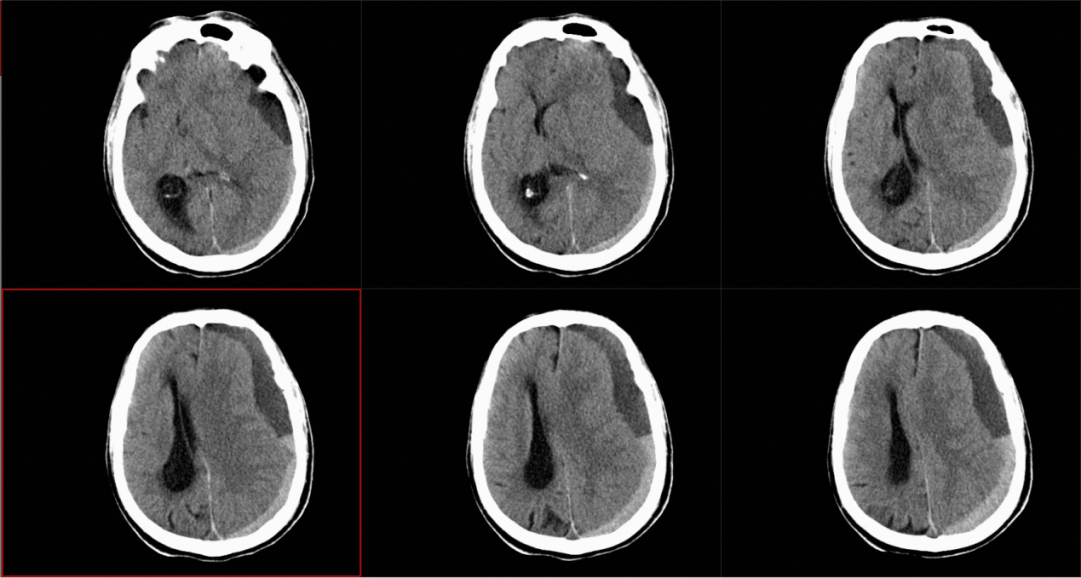

急診CT影像,見左側硬膜下混雜慢性硬膜下血腫,中線受壓右移。

慢性硬膜下血腫這個聽起來有些專業的名詞,其實可以簡單理解為「大腦外面慢慢地出血」。

慢性硬膜下血腫就是發生在硬腦膜和蛛網膜之間的血腫,通常是頭部受到輕微外傷後,少量出血逐漸積累形成的「血包」,這個形成過程可能持續數周甚至數月。